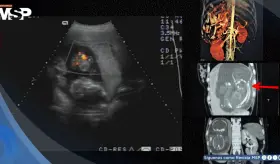

El aneurisma, detectado mediante una resonancia magnética, representaba un alto riesgo de ruptura y muerte, lo que obligó a una intervención urgente.